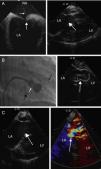

Elective PMBV was scheduled. Standard right heart catheterization was initially performed to invasively assess right heart pressures. Through a second right transfemoral venous access, the ICE catheter probe was advanced to the mid segment of the right atrium in order to visualize the atrial septum and guide the transeptal puncture. All septal borders were assessed before and during the tenting of the septum with the Mullin catheter (Figure 1A). After identification of the optimal interatrial septal position for puncture, the Brockenbrough needle and the sheath were advanced to the left atrium. With angiographic and ICE guidance the mitral valve balloon was advanced and inflated (Figure 1B). Immediate assessment of the post-procedural mitral valve morphology, transmitral valve gradient and mitral regurgitation were performed by fluoroscopy and ICE (Figure 1C).

(A) Left: ICE image showing tenting of the interatrial septum (large white arrow) with the Mullins catheter and Brockenbrough needle (small white arrow). LA: left atrium; RA: right atrium. Right: ICE 2-chamber view after insertion of the ICE probe into the right ventricle (RV). Visualization of the mitral valve (white arrow) prior to percutaneous mitral balloon valvuloplasty. Left atrial enlargement and left ventricular function and dimensions can be assessed. (B) Percutaneous mitral balloon valvuloplasty. Angiographic and ICE visualization of the inflated Inoue balloon (white arrow). ICE catheter probe (large black arrow) is located in the RV and the pig-tail catheter (small black arrow) in the left ventricle. (C) Post-PMBV ICE assessment. Left: two-dimension assessment. Right: Doppler evaluation of the mitral valve showing 1+ mitral regurgitation.